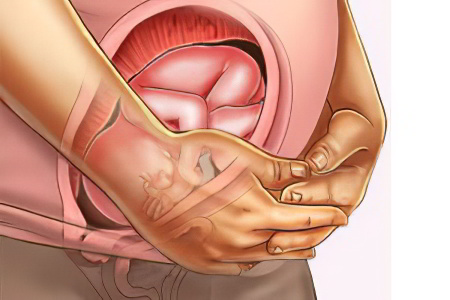

Что происходит с маткой?

Дно матки на 24 неделе беременности располагается на уровне пупка и это далеко не предел. По мере роста плода матка будет подниматься все выше. Шейка матки заполняется слизистой пробкой, которая отойдет только перед родами или во время них.

Матка может сокращаться, но эти сокращения в норме не должны быть длительными или болезненными. Таким образом она готовиться к предстоящим родам. Врачи называют подобные сокращения матки тренировочными схватками или схватками Брекстона-Хиггса.

Обязательно нужно обратиться за врачебной помощью в том случае, если сокращения становятся болезненными, а на их фоне из влагалища появляются выделения (водянистые или с примесями крови). Чаще всего такая ситуация указывает на начало преждевременных родов.